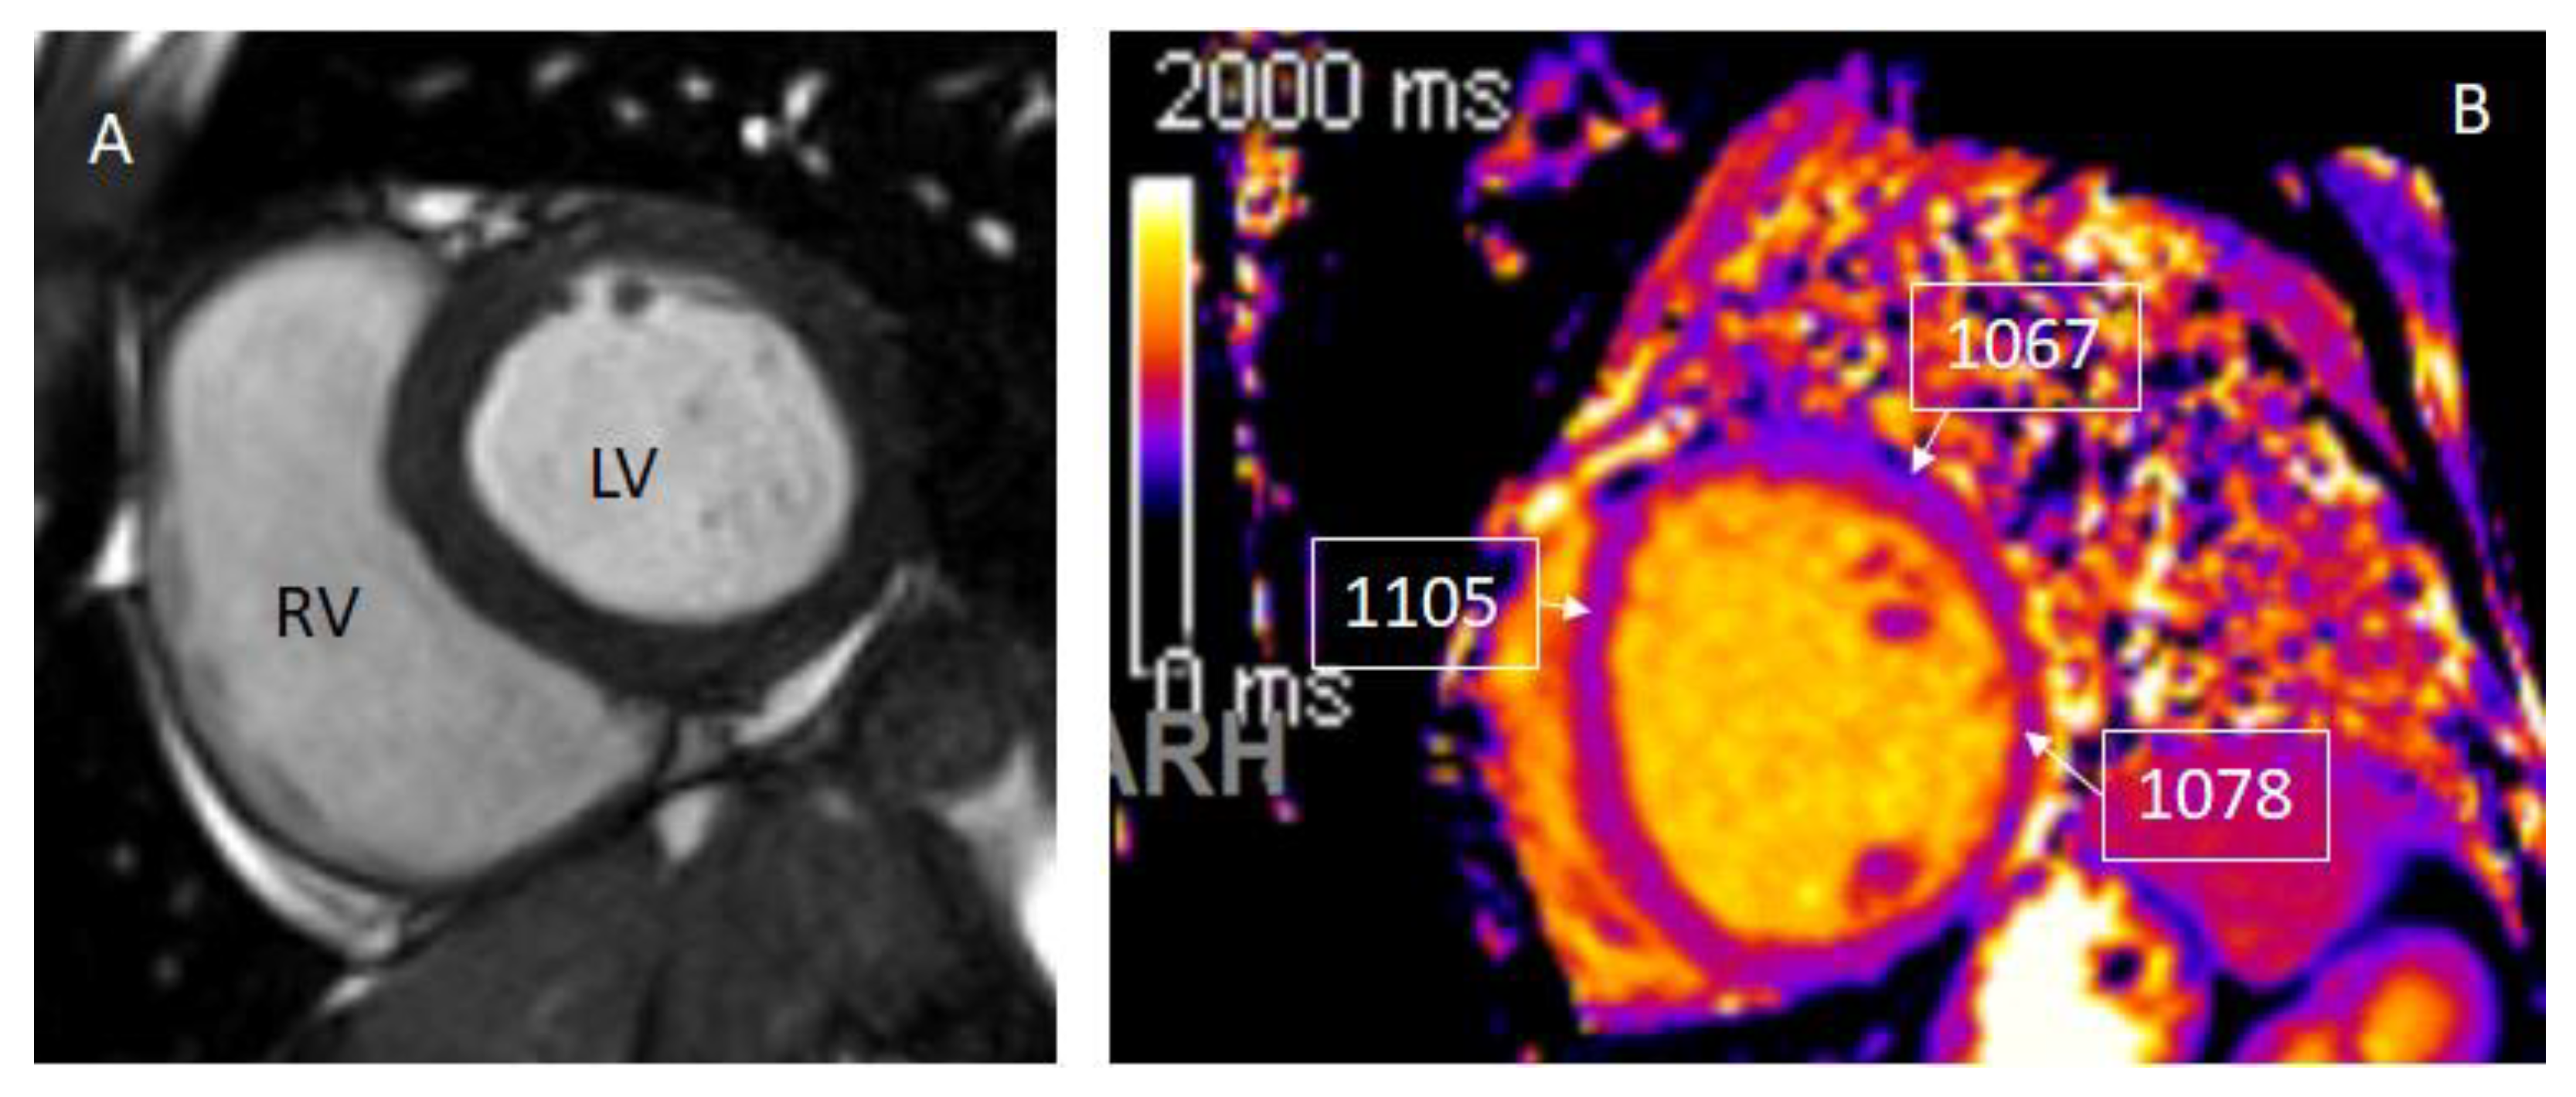

2. CMR Findings of Myocardial Inflammation and Pathological Correlations

3. CMR in Acute Myocarditis

4. CMR in Chronic Myocarditis